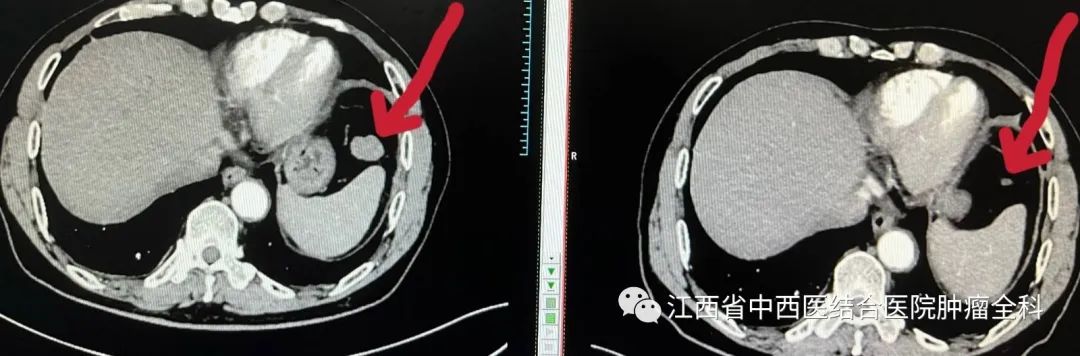

图4:2022年2月08日与2022年5月18日腹部CT

脾前缘膈下结节状软组织影治疗前后对比